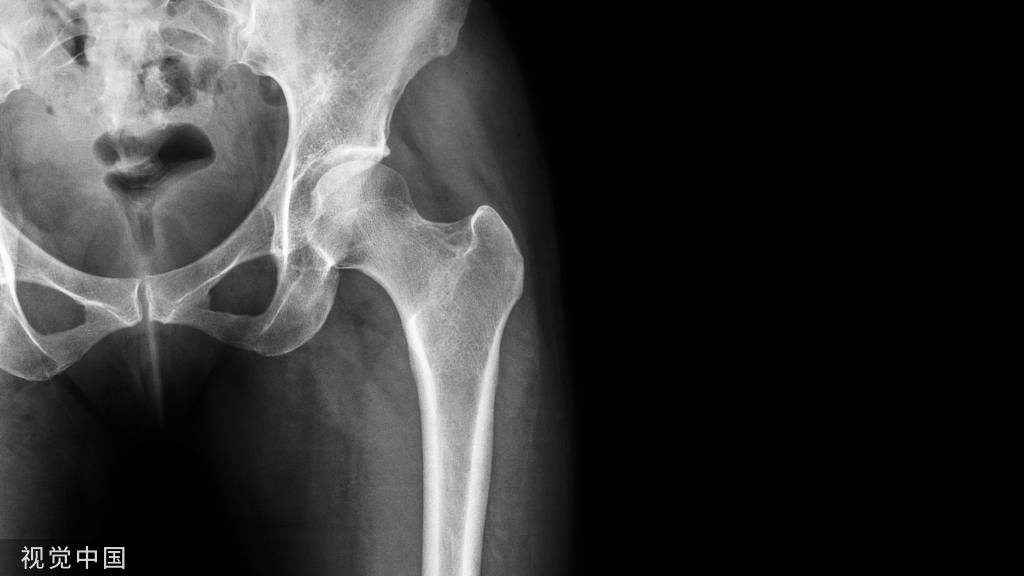

病例3:1例81岁女性患者,左外侧髋部和腹股沟疼痛。在初次全髋关节置换术前,体检记录为Trendelenburg步态和4/5的外展肌力。MRI显示肌腱病变和累及臀中肌和臀小肌腱的部分撕裂的征象。在初次全髋关节置换术中,在股骨近端的止点发现了臀中肌和臀小肌腱部分撕裂。全髋关节假体植入后,一期缝合修复。手术后,她恢复得很好,但最终在大转子上出现了越来越多的疼痛。检查中发现3-4/5外展肌力。手术切除异位骨化。外展肌经经骨隧道进行部分修复,并通过臀大肌和阔筋膜张肌的转移来加强修复。

(A-C)术前X光显示先前植入的右侧全髋关节假体,包括非骨水泥的股骨柄和非骨水泥的髋臼假体。(D和E)外展肌重建后12个月MRI图像显示臀中肌、臀小肌、臀大重建瓣和阔筋膜张肌重建瓣完整。患者报告的外展肌重建术22个月的结果包括:静息疼痛,1/10;行走疼痛,3/10;Harris髋关节评分,58;牛津髋关节评分,23。病人报告说,走路时有轻微的跛行和拐杖。